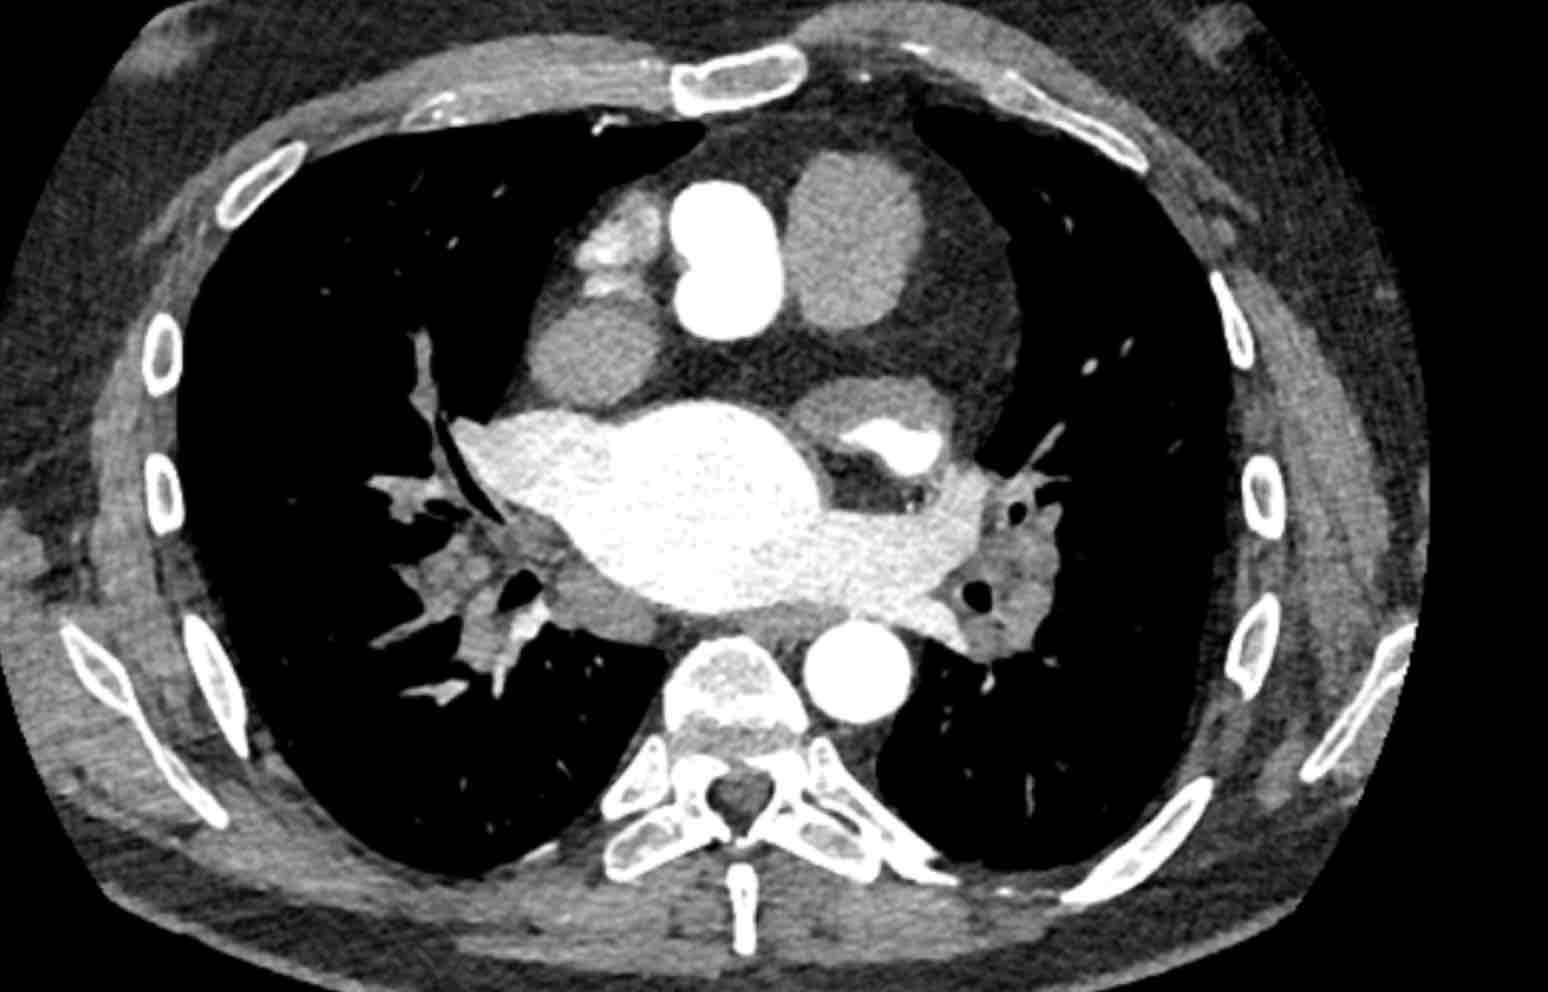

Hình ảnh

Huyết khối bám thành trung tâm ở bệnh nhân bị bệnh huyết khối tắc mạch mạn tính kèm giãn buồng tim phải, phù hợp với tăng áp động mạch phổi do huyết khối tắc mạch mạn tính (CTEPH).